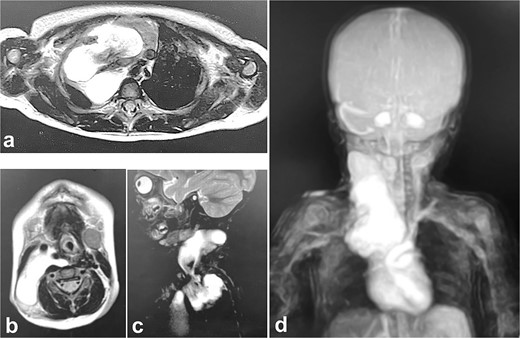

Pathologic findings on the first administration. The tumor size in the cervical region was quite large and there may be a risk of airway system compression. (a) physical finding, (b) chest X-ray, (c) plain computed tomography.